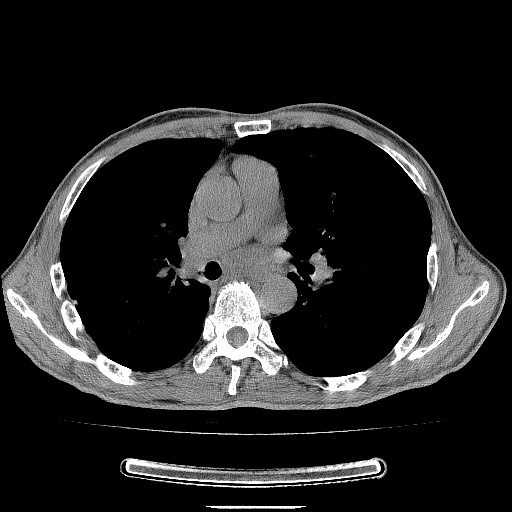

男性患者,63岁。右侧胸背部疼痛2月,加重一周。

考虑:右肺中央型肺癌并右肺下叶不张;两肺尖继发性肺结核。

右肺下叶支气管狭窄闭塞,右下肺不张,气管前间隙淋巴结肿大,两上肺散在分部粟粒灶,沿肺血管支气管束分部,血管支气管束走形较为光滑。考虑右肺中心型肺癌合并肺不张,纵隔淋巴结转移,两上肺癌性淋巴管炎

右肺下叶中心性肺癌并纵隔淋巴结转移,左侧肋骨转移。双肺上叶继发性结核表现。